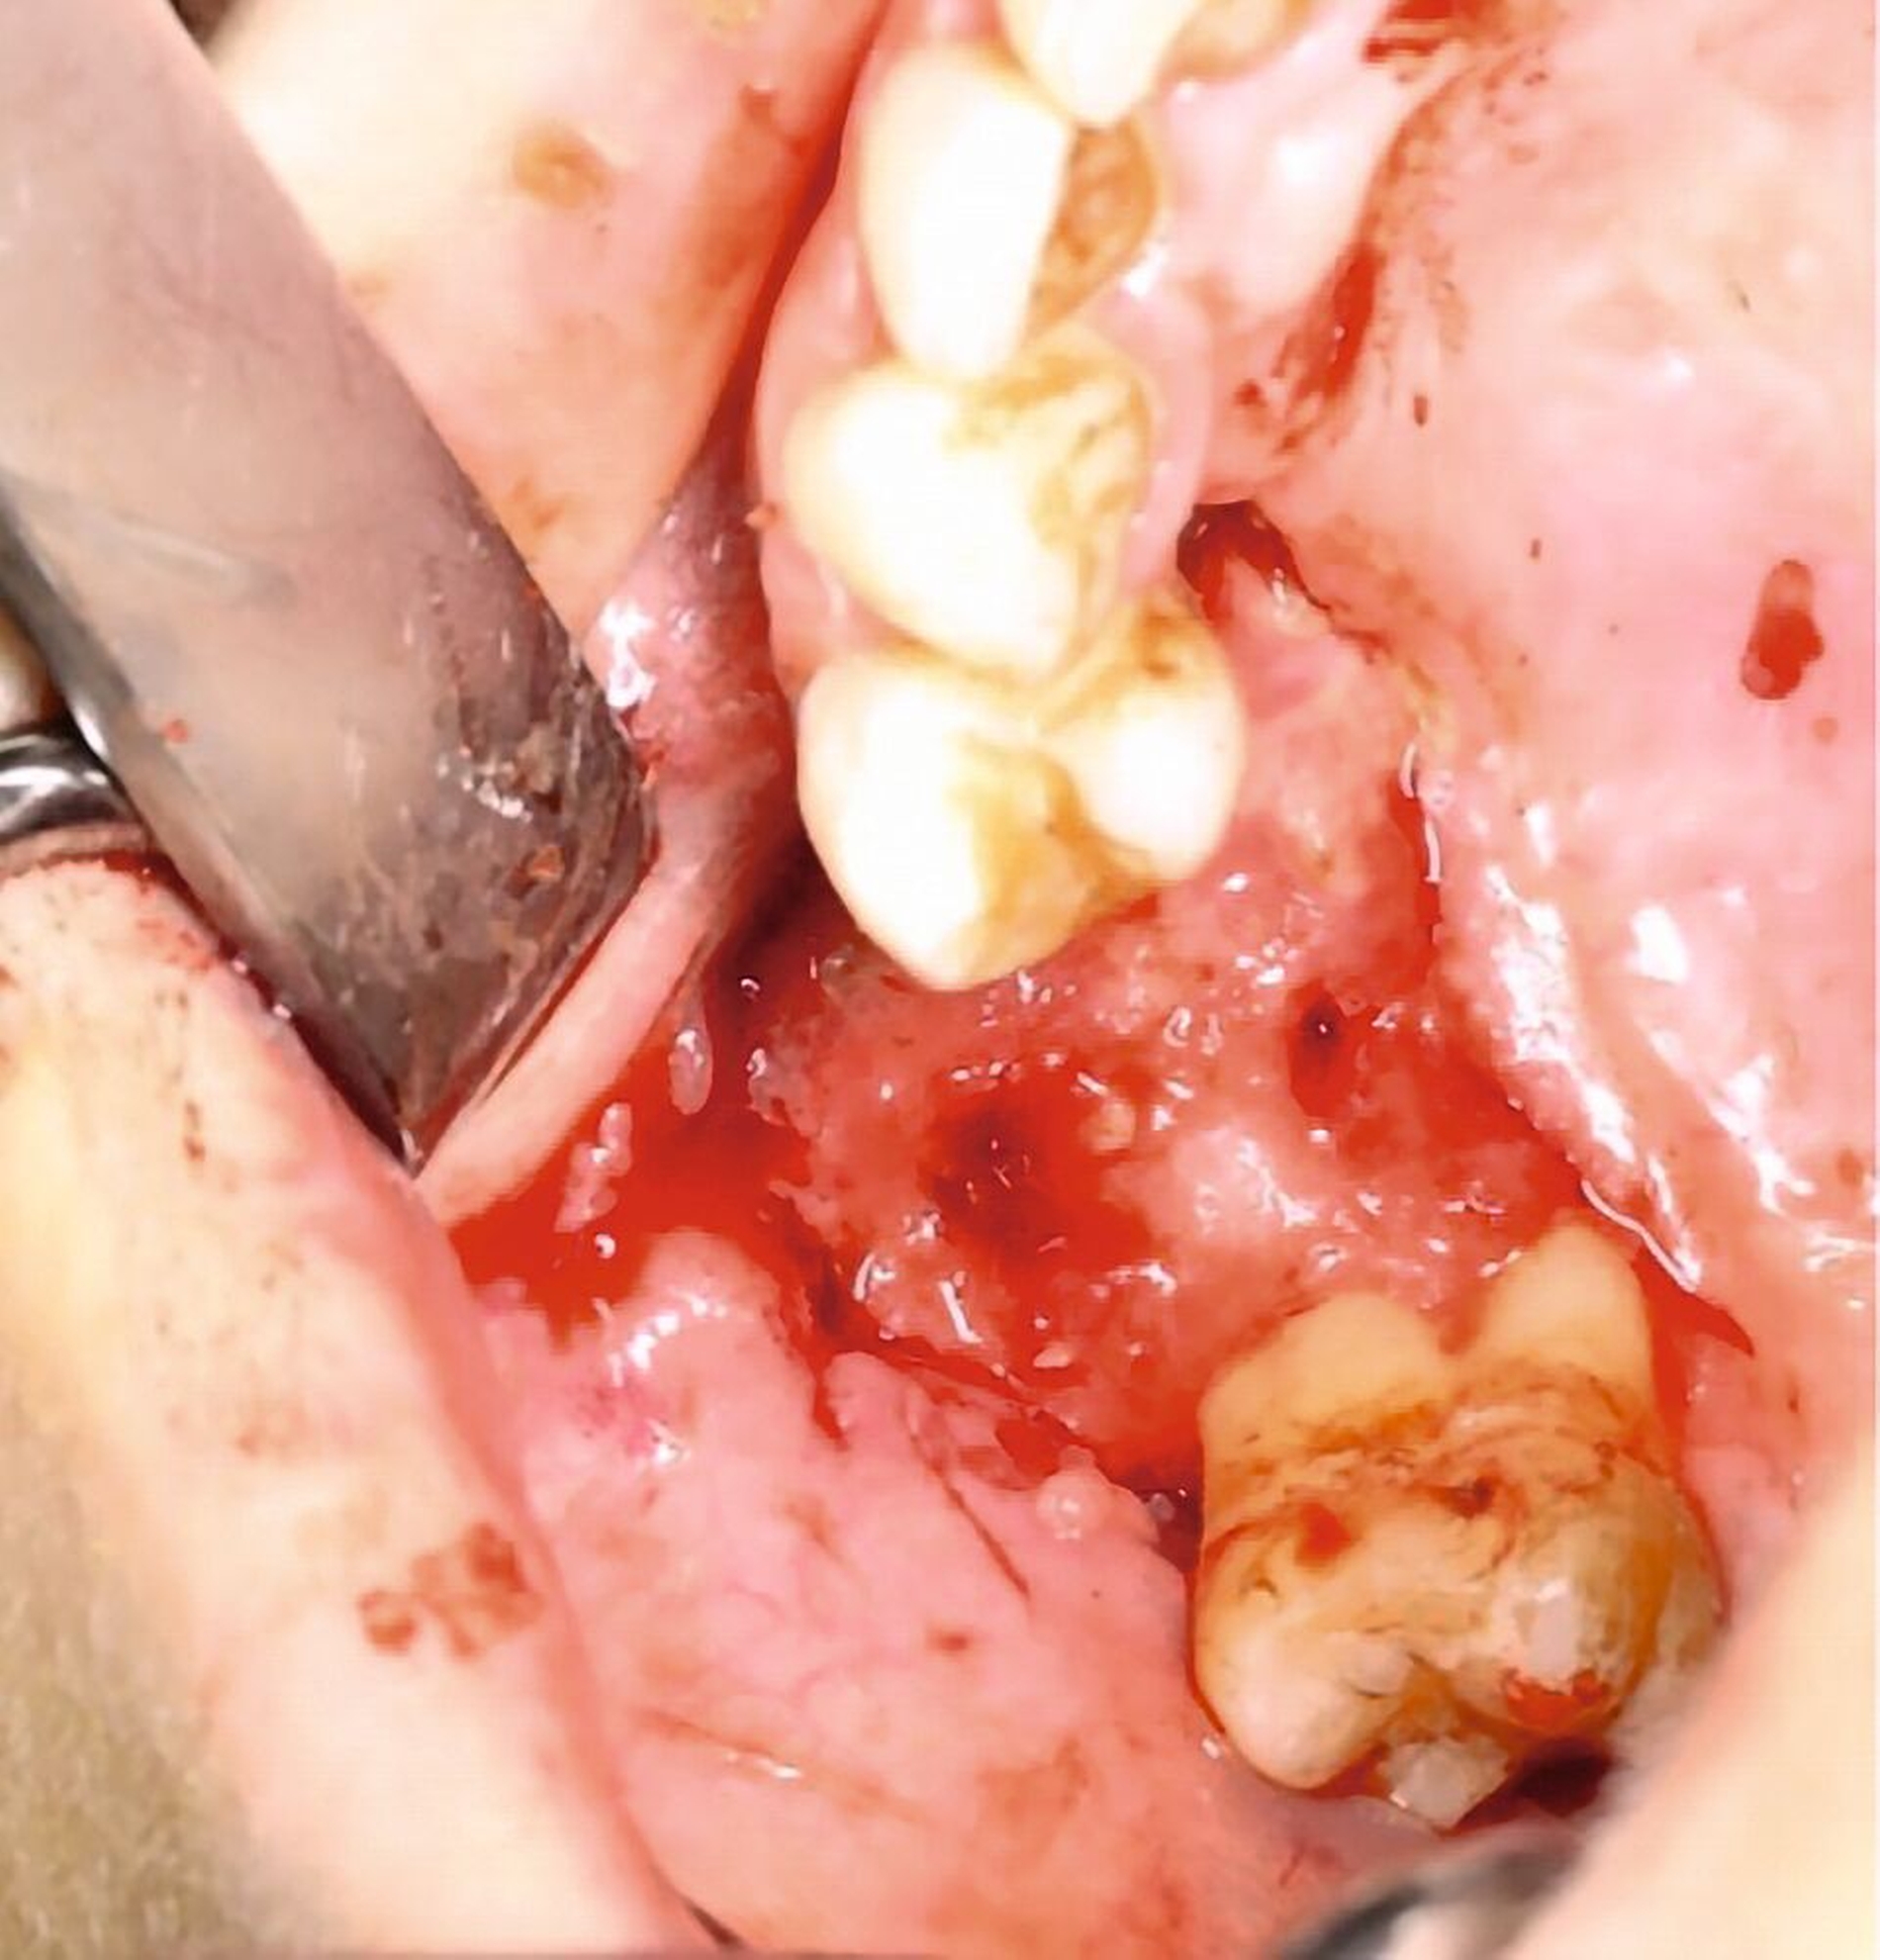

Die klinische Untersuchung zeigte eine ausgeprägte nekroische Schleimhaut palatinal und vestibulär regio 15 bis 17, einen stark gelockerten Zahn 15 sowie einen intensiven Foetor ex ore bei einer auf 2,5 cm eingeschränkten Mundöffnung (Abbildung 1).

Das DVT zeigte eine Spiegelbildung im rechten Sinus maxillaris, jedoch keinen stark auffälligen knöchernen Befund (Abbildung 2). Die Patientin wurde zu intravenöser Antibiose, Analgesie und Ernährung über eine nasogastrale Sonde stationär aufgenommen. Im Verlauf wurde eine Verbandsplatte per Intraoralscan angefertigt und eine Operation zur Nekrosektomie und Wundanfrischung geplant. Zum Zeitpunkt des operativen Eingriffs hatten sich bereits Teile der vestibulären und der palatinalen Schleimhaut abgelöst. Nach Debridement zeigte sich ein großflächiges Areal mit freiliegendem Knochen. Der Zahn 15 wurde bei Lockerungsgrad III entfernt (Abbildung 3).